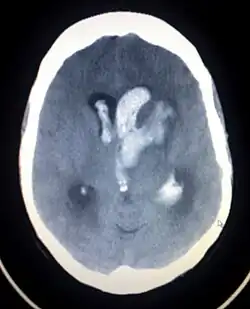

Axiali CT scan of a spontaneous intracranial hemorrhage | |

A non-contrast CT scan (computed tomography) of the brain is commonly used as the initial imaging modality in suspected cases of intracranial hemorrhage. CT is preferred in emergency settings due to its speed, availability, and high sensitivity for detecting acute brain injuries, enabling rapid triage and surgical decision-making. Examples of brain diseases that require urgent intervention are: large-volume hemorrhage, brain herniation, and cerebral infarction. Additional advantages of CT imaging include its effectiveness in detecting bony fractures, vascular injuries, and cerebrospinal fluid (CSF) leaks.

A swirl sign on CT imaging— representing areas of low density with surrounding areas of high density— suggest active intracranial bleeding. The presence of this sign is associated with an increase in risk of death within one month and a poor functional prognosis at three months among survivors.[6]

The size of the hemorrhage can vary, ranging from small, asymptomatic lesions to large hematomas causing mass effect and increased intracranial pressure. Follow-up CT imaging is recommended to monitor hematoma expansion, ventricular extension, or progressive cerebral edema, all of which are associated with poorer outcomes.